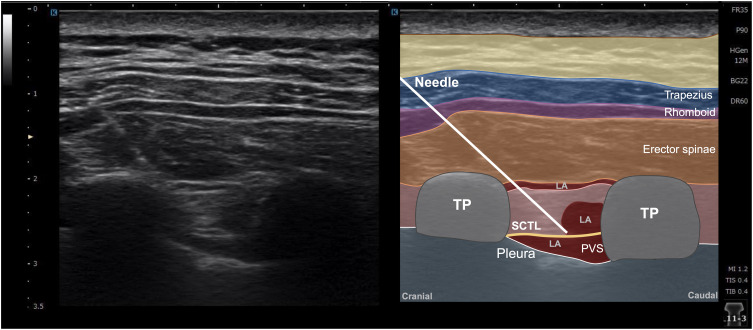

Purpose: While the intertransverse process (ITP) block can enhance chest wall analgesia, the optimal injection technique remains unclear. This study compared the efficacy of single versus multiple injections of the ITP block, hypothesizing that multiple injections would provide superior sensory blockade.

Patients and methods: Forty patients undergoing video-assisted thoracic surgery were randomized to receive single or multiple ultrasound-guided ITP block injections with 30 mL of 0.25% bupivacaine and 1% lidocaine with epinephrine (5 μg/mL). The single-injection group received 30 mL at the T4-5 level, while the multiple-injection group received 10 mL/injection at the T3-4, T4-5, and T5-6 levels. The primary outcome was dermatomal sensory changes on the anterolateral chest wall. Secondary outcomes included block performance time, complications, and postoperative analgesia.